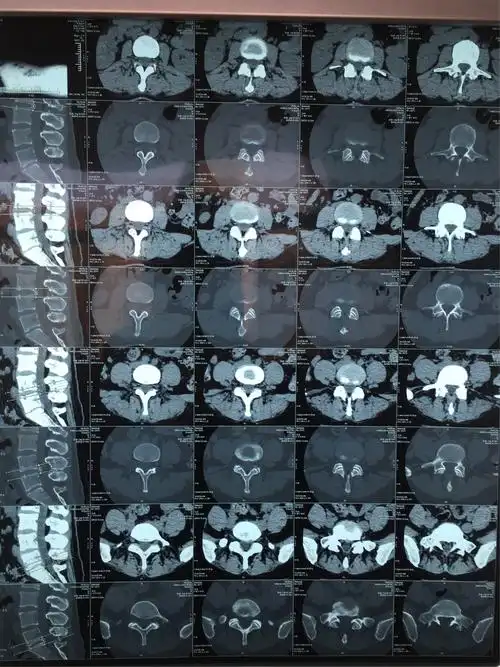

腰间盘突出片子怎么看

旁中央型腰间盘突出症病人.39岁女性病人

术前影像学资料:从患者的片子可以明显看出,腰4-5椎间盘出现突出,继发